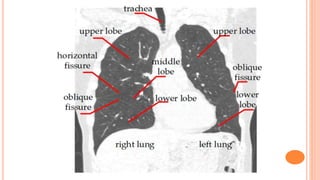

Fissures

• #33 So you should compare the lung parenchyma left to right in the upper, middle and lower zones and see whether there is a difference. Look for equal radiolucency between the left and the right lungs zones. The horizontal fissure on the right divides the upper and middle lobes; from the hilum to the 6th rib at the axillary line. You should also check soft tissues outside the thorax for subcutaneous air, foreign body, bizarre density, etc.